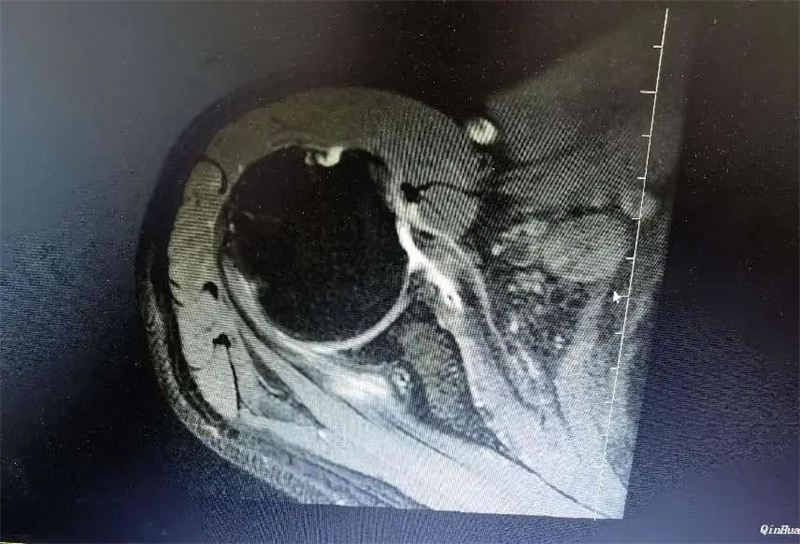

10月15日,秦皇岛41岁的张姓患者因骑车时摔伤导致右肩活动受限十余天,通过多方了解来到军工医院运动医学科就诊。运动医学科薛朝亚主任和孙超主治医师详细询问患者情况及症状。患者由于受伤以来不敢活动,继发肩关节粘连,肩关节活动度差,关节间隙不好,肩袖撕裂回缩严重,已经从正常的肱骨大结节回缩至肩胛盂上,合并肱二头肌腱脱位、肩胛下肌完全撕裂,回缩粘连,属于复杂型巨大肩袖撕裂。

肩袖是包绕在肱骨头周围的一组肌腱复合体,包括冈上肌腱、冈下肌腱、肩胛下肌腱和小圆肌腱,这些肌腱将肱骨头稳定于肩胛盂上,对维持肩关节的稳定和肩关节活动起着极其重要的作用。其中冈上肌主要负责上抬肩关节、和下压肱骨头的作用,撕裂后主要表现为疼痛和抬肩无力,肩胛下肌主要负责肩关节内旋,损伤后主要表现为内旋无力与疼痛,患者因肩袖损伤后继发关节粘连,需手术治疗。运动医学科医疗团队经术前讨论后制定手术方案,孙超医生与患者及家属详细沟通,确定手术治疗。 术前准备完毕,手术开始。医生将患者肩关节囊、肌腱松解后分别行肩胛下肌修复、肱二头肌腱固定术与冈上肌修复术。在兄弟科室的配合下,手术取得圆满成功。